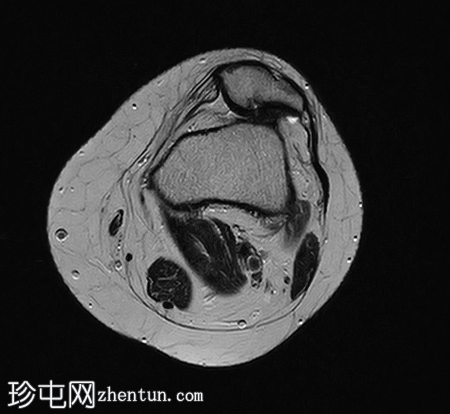

轴位

T2加权像

9.png

髌骨高位(Insall-Salvati比值=1.7),伴外侧半脱位。内侧髌骨支持带及内侧髌股韧带变薄、缺损、松弛。

外侧髌骨关节面软骨内T2/STIR/PD信号强度增高,伴下方骨髓囊性改变和水肿。

外侧Hoffa脂肪垫水肿。

外侧髌骨关节面软骨软化。